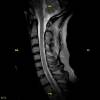

En nuestros centros se realizan estudios y diagnósticos de resonancia magnética musculo-esquelética

de Resonancia ,Magnética Musculo-Esquelética, de la marca italiana Esaote, es único en su diseño ya que nos permite realizar exámenes en bipedestación (el paciente estará de pie, para que se tenga otra perspectiva del comportamiento del cuerpo durante el examen).